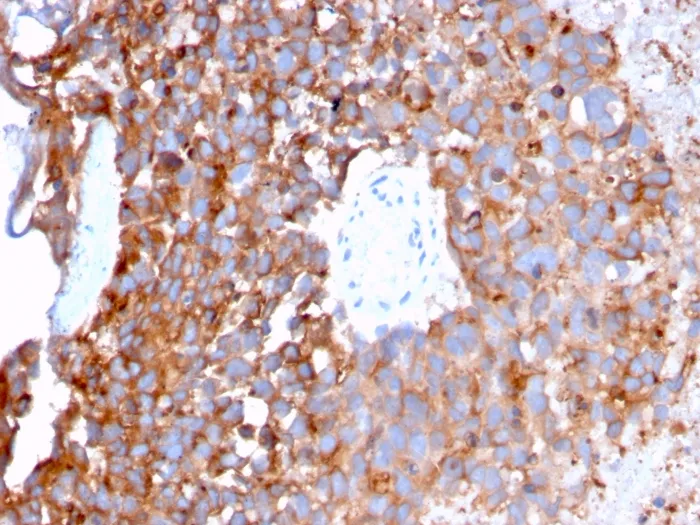

Anti-Uroplakin 1B (Urothelial Differentiation Marker)(UPK1B/3273)

Anti-Uroplakin 1B (Urothelial Differentiation Marker)(UPK1B/3273)

The protein encoded by this gene is a member of the transmembrane 4 superfamily, also known as the tetraspanin family. Most of these members are cell-surface proteins that are characterized by the presence of four hydrophobic domains. The proteins mediate signal transduction events that play a role in the regulation of cell development, activation, growth and motility. This encoded protein is found in the asymmetrical unit membrane (AUM) where it can form a complex with other transmembrane 4 superfamily proteins. It may play a role in normal bladder epithelial physiology, possibly in regulating membrane permeability of superficial umbrella cells or in stabilizing the apical membrane through AUM/cytoskeletal interactions. UPK1B is expressed by terminally differentiated urothelial cells. Primary antibodies are available purified, or with a selection of fluorescent CF® Dyes and other labels. CF® Dyes offer exceptional brightness and photostability. Note: Conjugates of blue fluorescent dyes like CF®405S and CF®405M are not recommended for detecting low abundance targets, because blue dyes have lower fluorescence and can give higher non-specific background than other dye colors.Synonyms:

IHC, FFPE (verified)Validated Applications:

IHC, FFPEPositive Control: